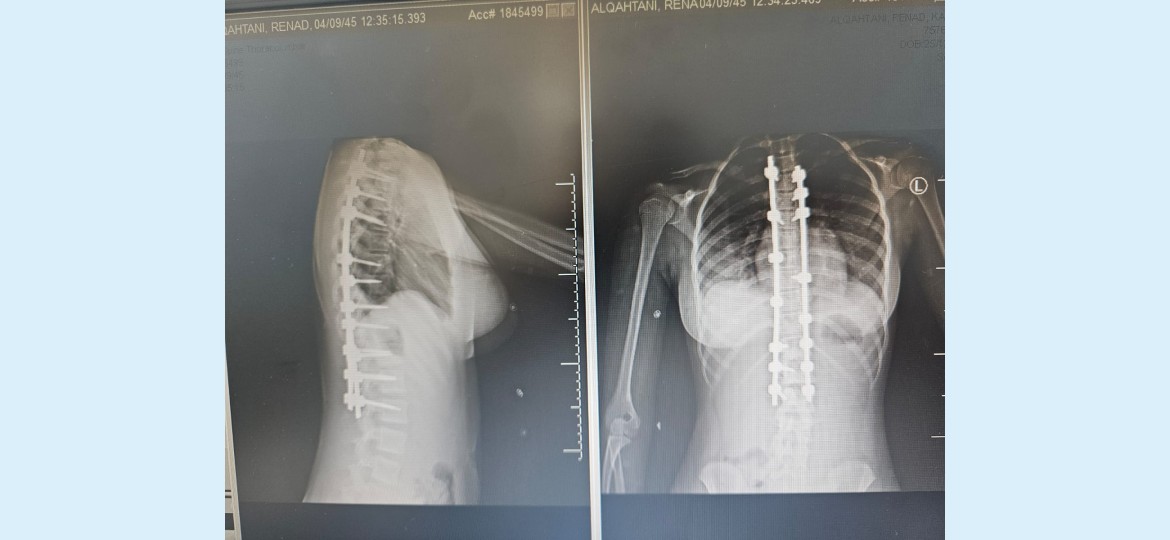

نجح فريق طبي متخصص في قسم جراحة العمود الفقري بمستشفى الملك عبدالله في بيشة من أجراء عملية (جنف) لطفلة تبلغ من العمر 13 سنة، وذلك بعد معاناتها من تشوه بالظهر منذ الولاده.

وأوضح تجمع عسير الصحي نطاق بيشة ، أن الطفله حضرت إلى المستشفى وبعد عمل الأشعة والتحاليل اللازمة شٌخصت الحالة على أنها جنف شديد مع وجود صعوبة في أداء وممارسة الأنشطة اليومية ومشكلات في النوم نتيجة إصابتها بانحرافٍ شديدٍ في العمود الفقري (الجنف) منذ الطفوله.

وأضاف التجمع : انه وبعد دراسة ملف الطفله قرر الفريق الطبي المعالج ، المكون من الدكتور صالح ال خبتي استشاري جراحة العمود الفقري، والدكتور احمد البنداري أخصائي جراحة العمود الفقري والدكتور اكينبو أخصائي جراحة العمود الفقري، والدكتوره نادر بدوي استشاري تخدير من أجراء عملية التدخل الجراحي لعلاج هذه العيوب والحد من المضاعفات، حيث تمّ إجراء عملية استقامة العمود الفقري بشكل عمودي وتثبيت ودمج الفقرات، بعد ذلك خضعت المريضة لبرنامج علاج طبيعي مكثّف لتقوية عضلات الظهر والفقرات.